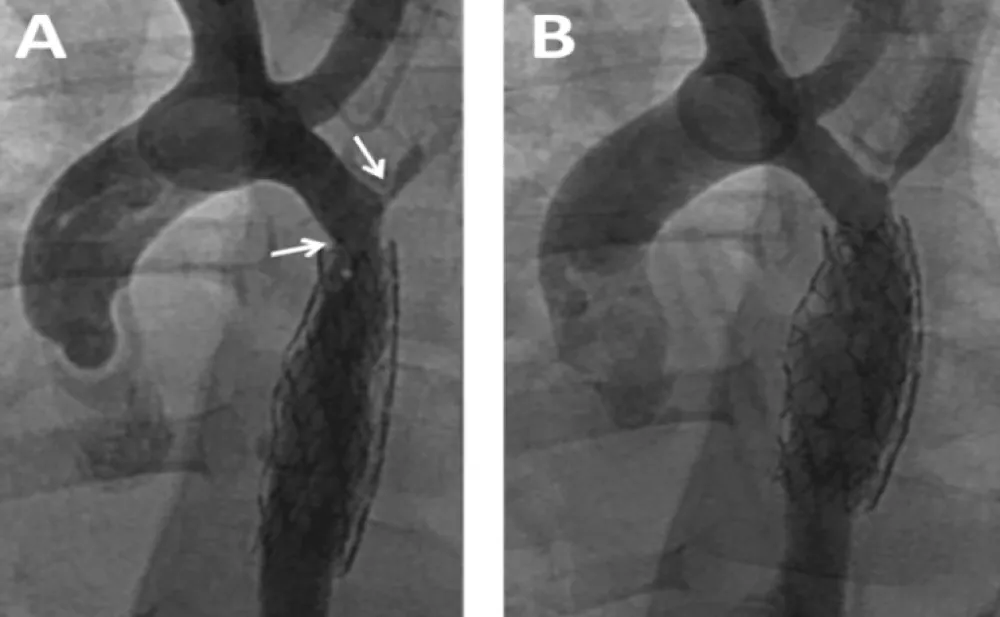

Enalapril was continued and dual anti aggregation was started with clopidogrel and aspirin. On follow-up the femoral pulses were weaker than the right brachial. Blood pressures could not be measured for persistent excessive irritability. At the time of multislice CT under general anesthesia, noninvasive blood pressure showed normal values for the right arm and moderate increase in the coarctation gradient (Table 1). CT imaging findings were no different to those following BA. The descending aorta distal to the stent remained narrowed reassuming a normal caliper at the diaphragm level. Two more BAs for recurrent coarctation were performed at age 3y 5m and 5m later. The former with right axillary artery access for recoarctation distal to the left subclavian artery which had severe ostial stenosis and subclavian steal (Figure 4A). The intrastent intimal proliferation was much less prominent than in the previous procedure and the coarctation diameter almost doubled (Figure 4B). The other intervention from the right femoral artery addressed the sub-clavian stenosis with disappearance of subclavian steal. The patient continues with antihypertensive and dual antiaggregation therapy. An extended patch angioplasty is expected in the future (Figure 4 A,B).

Figure 4: Balloon Angioplasty for Recurrent Coarctation at age 41 months. A: Recurrent coarctation proximal to the stent (left arrow). Severe stenosis at the origin of the left sub-clavian artery (right arrow). Intrastent proliferation much less evident than in previous procedure; B: Successful dilatation of the coarctation with right axillary approach. The sub-clavian stenosis was addressed with femoral artery approach in a following procedure.